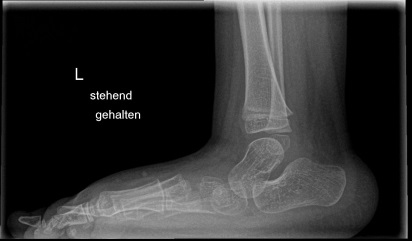

Röntgen Fuß AP und seitlich im Stand oder belastungssimuliert (Abb.1,2).

Röntgen seitlich in maximaler Plantarflexion bei Unklarheit über die Flexibilität.

Standaufnahme des oberen Sprunggelenkes: Bei Verdacht auf Instabilität oder Fehstellung des oberen Sprunggelenkes.